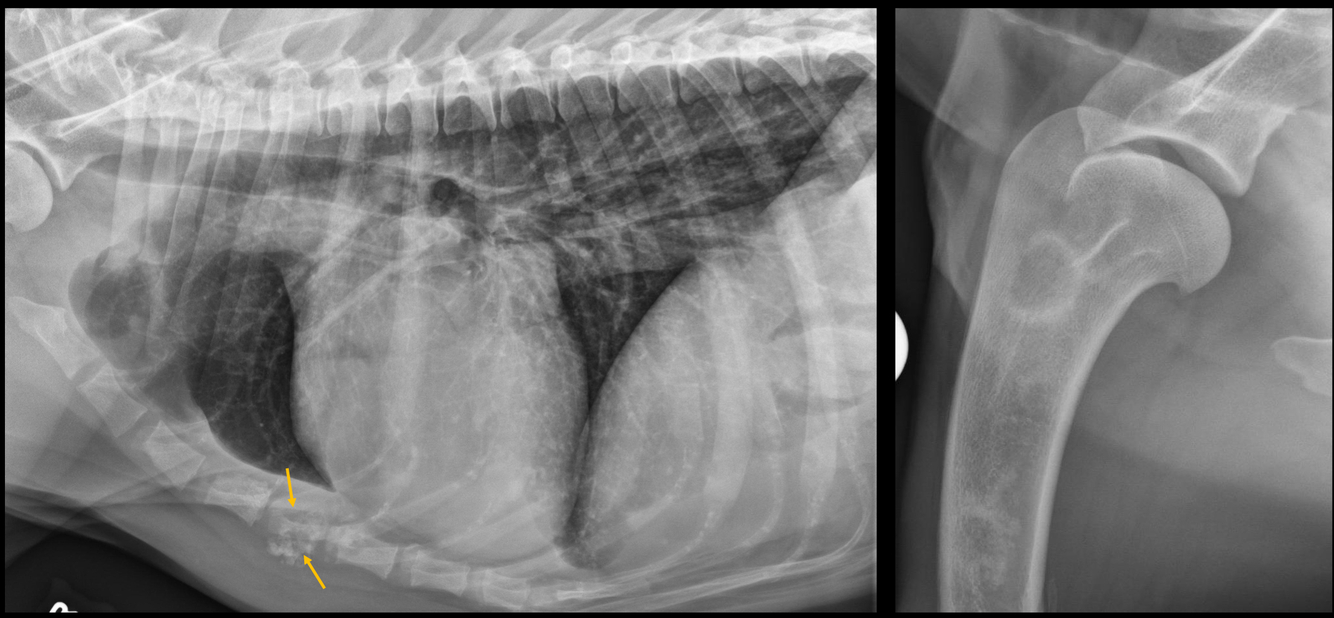

Q

What is occurring in this radiograph?

A

• left crura is cranial on a right lateral projection

• gas and mineral opacity indicative of ingesta = herniated intestine in thorax!

(secondary to diaphragmatic rupture)